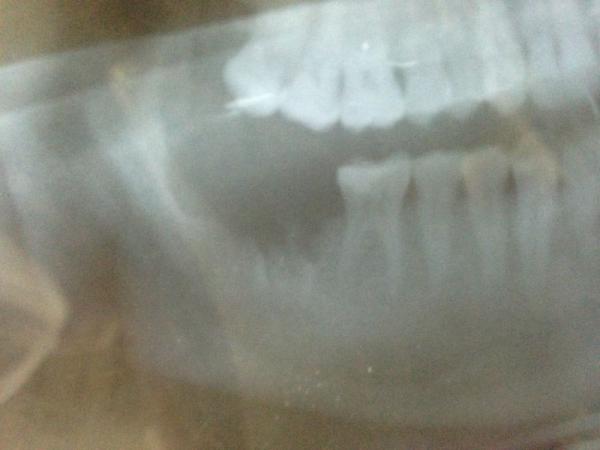

A pensioner had his dentures stuck in his throat for over a week after a surgery mishap.

The 72-year-old anonymous man had undergone an operation to remove a harmless lump in his abdominal wall, but he had to return to the unnamed hospital six days later after finding it difficult and painful to swallow food, while he also had blood in his mouth.

The BMJ Case Reports medical journal has revealed how doctors initially sent him home prescribing mouthwash, antibiotics and steroids to treat the suspected effects of having a tube down his throat, but two days later he returned with worsening symptoms.

Doctors then found the dentures, which "had been lost during general surgery admission" eight days earlier.

He was taken for emergency surgery to remove the object, and got discharged six days later.